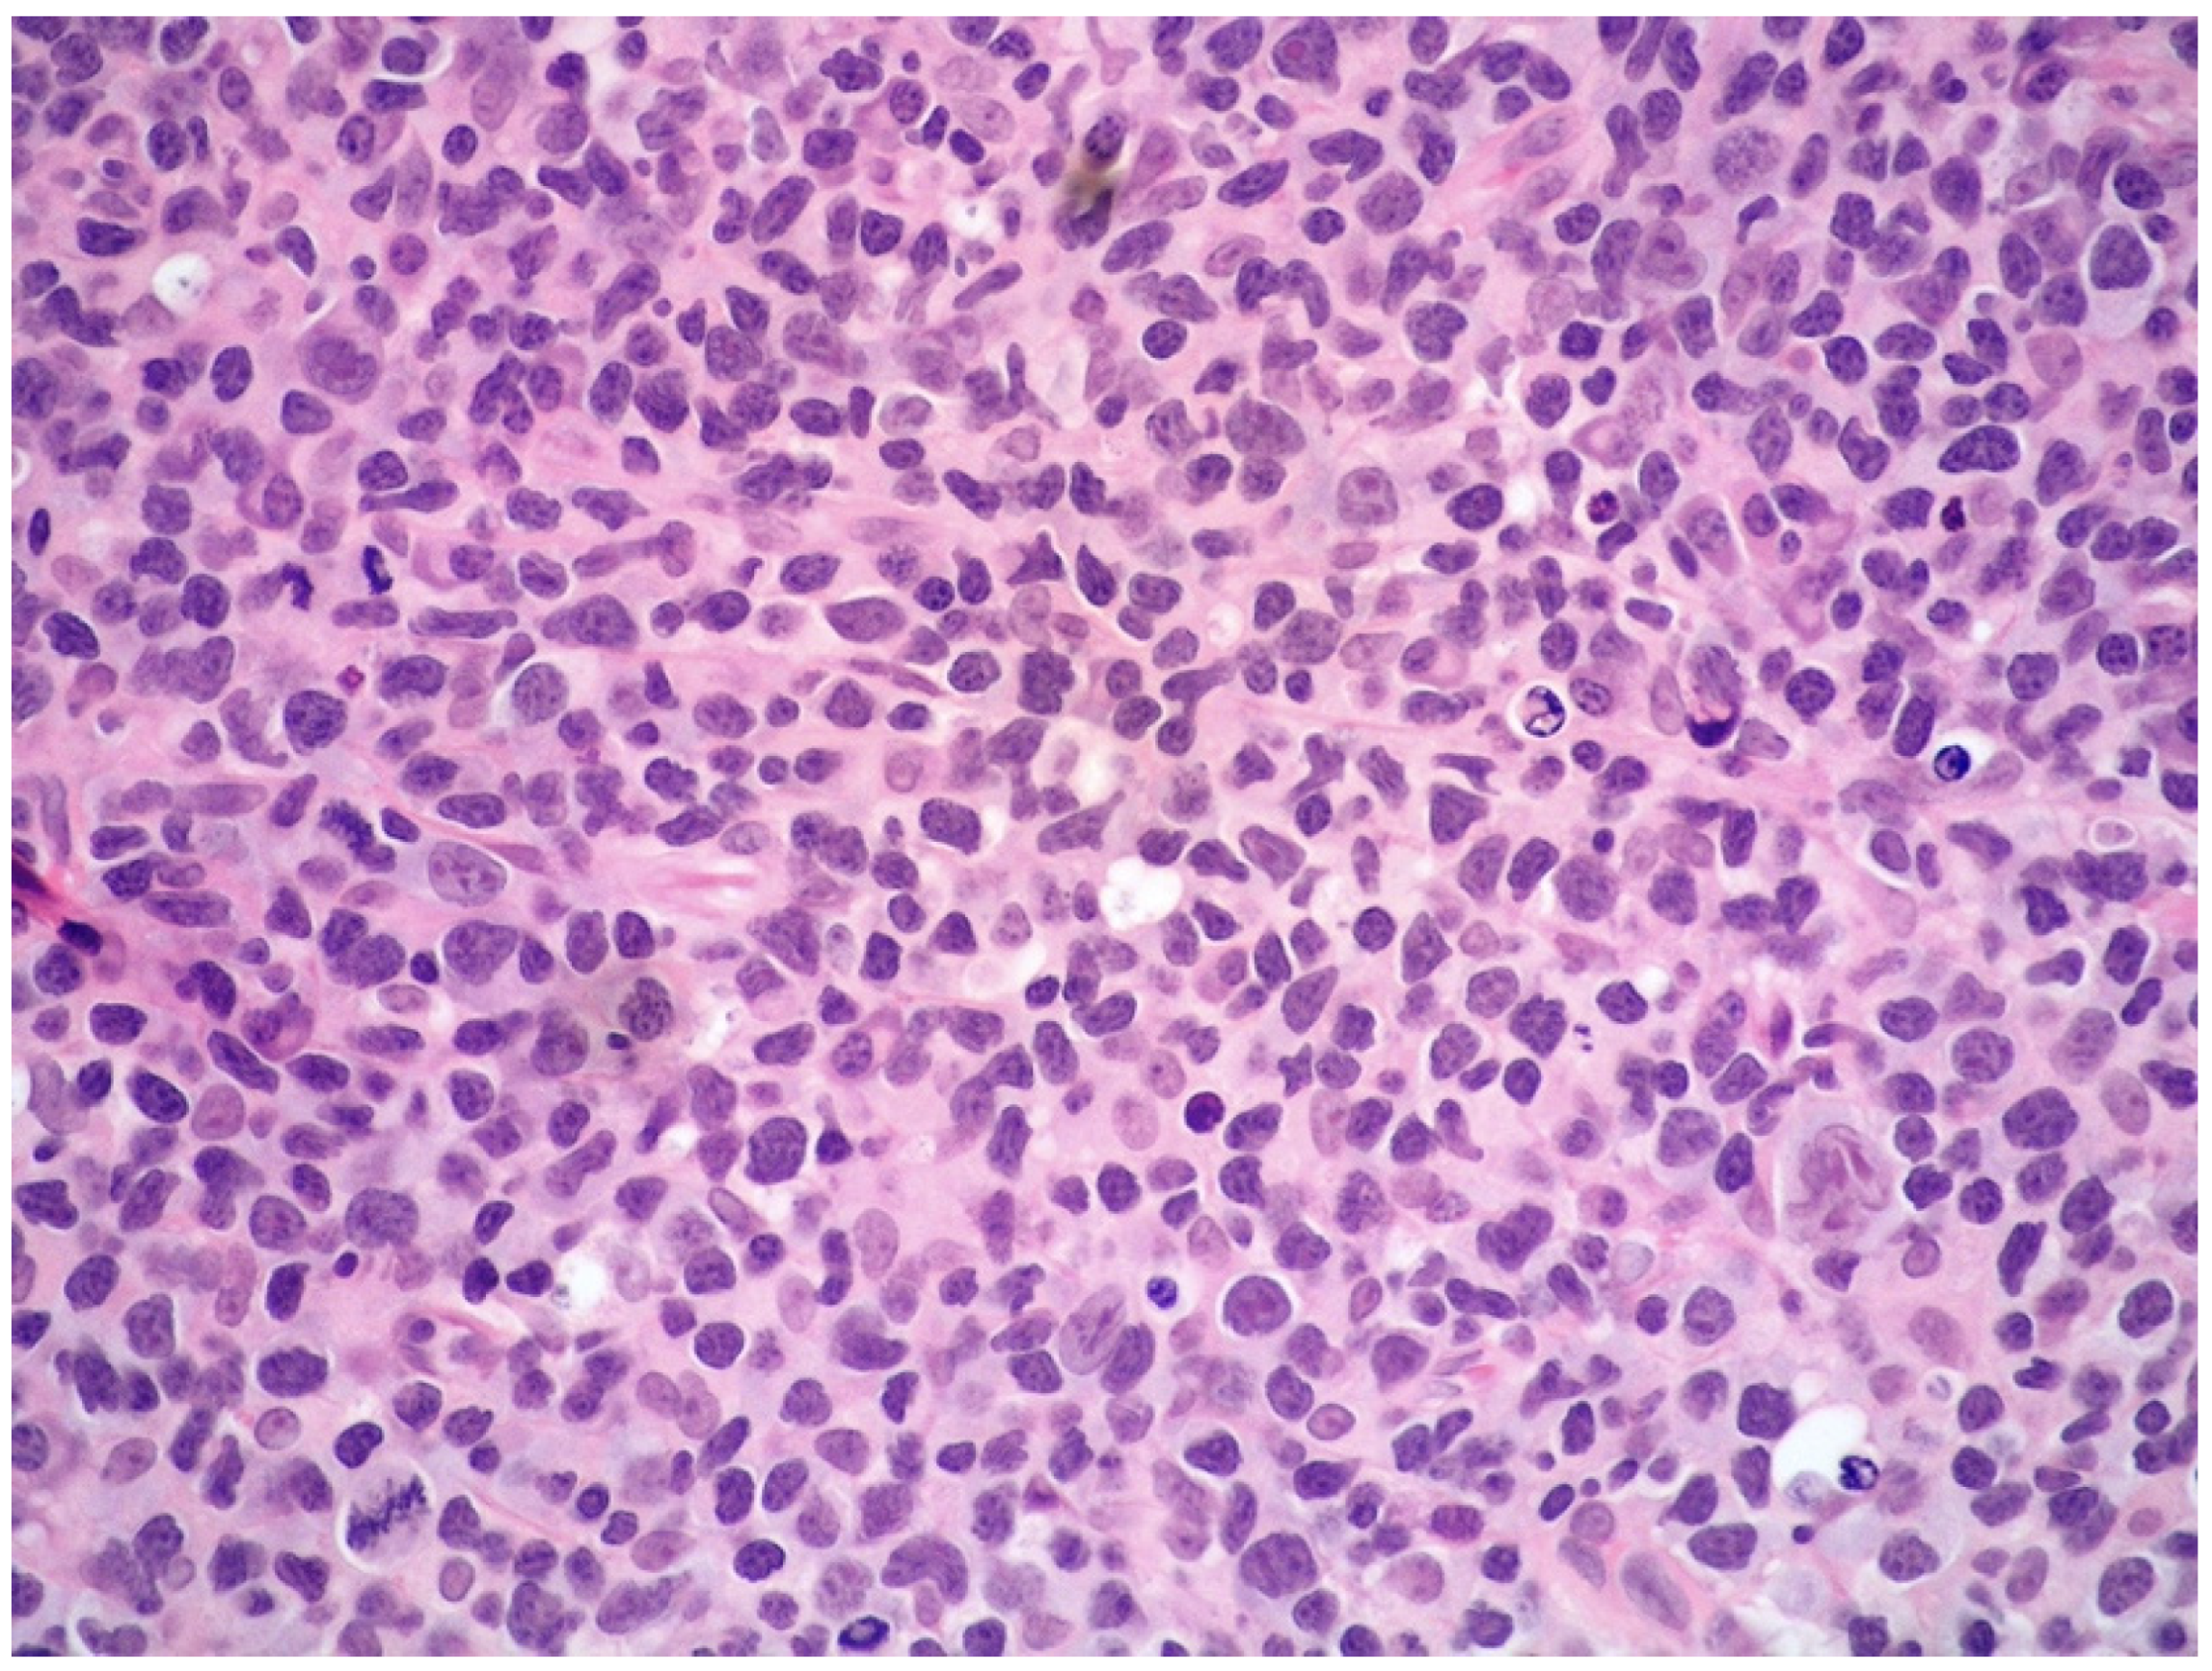

The neoplastic elements are rather polymorphic and variable in size, although small- to medium-sized cells with scarce and clear cytoplasm, irregular nucleus, granular chromatin, and inconspicuous nucleolus are generally prevalent. Large-sized lymphoid cells may be present. Mitotic figures are frequent. (Figure 6).

Figure 6.

High-power view showing a diffuse and polymorphic proliferation of atypical, medium- to large-sized lymphoid cells (hematoxylin and eosin, 200× magnification, previously unpublished, original image from S.A.).